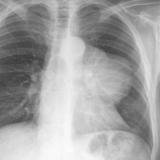

Case 8a Thymoma PA

Date: 03/27/2009

Views: 9457